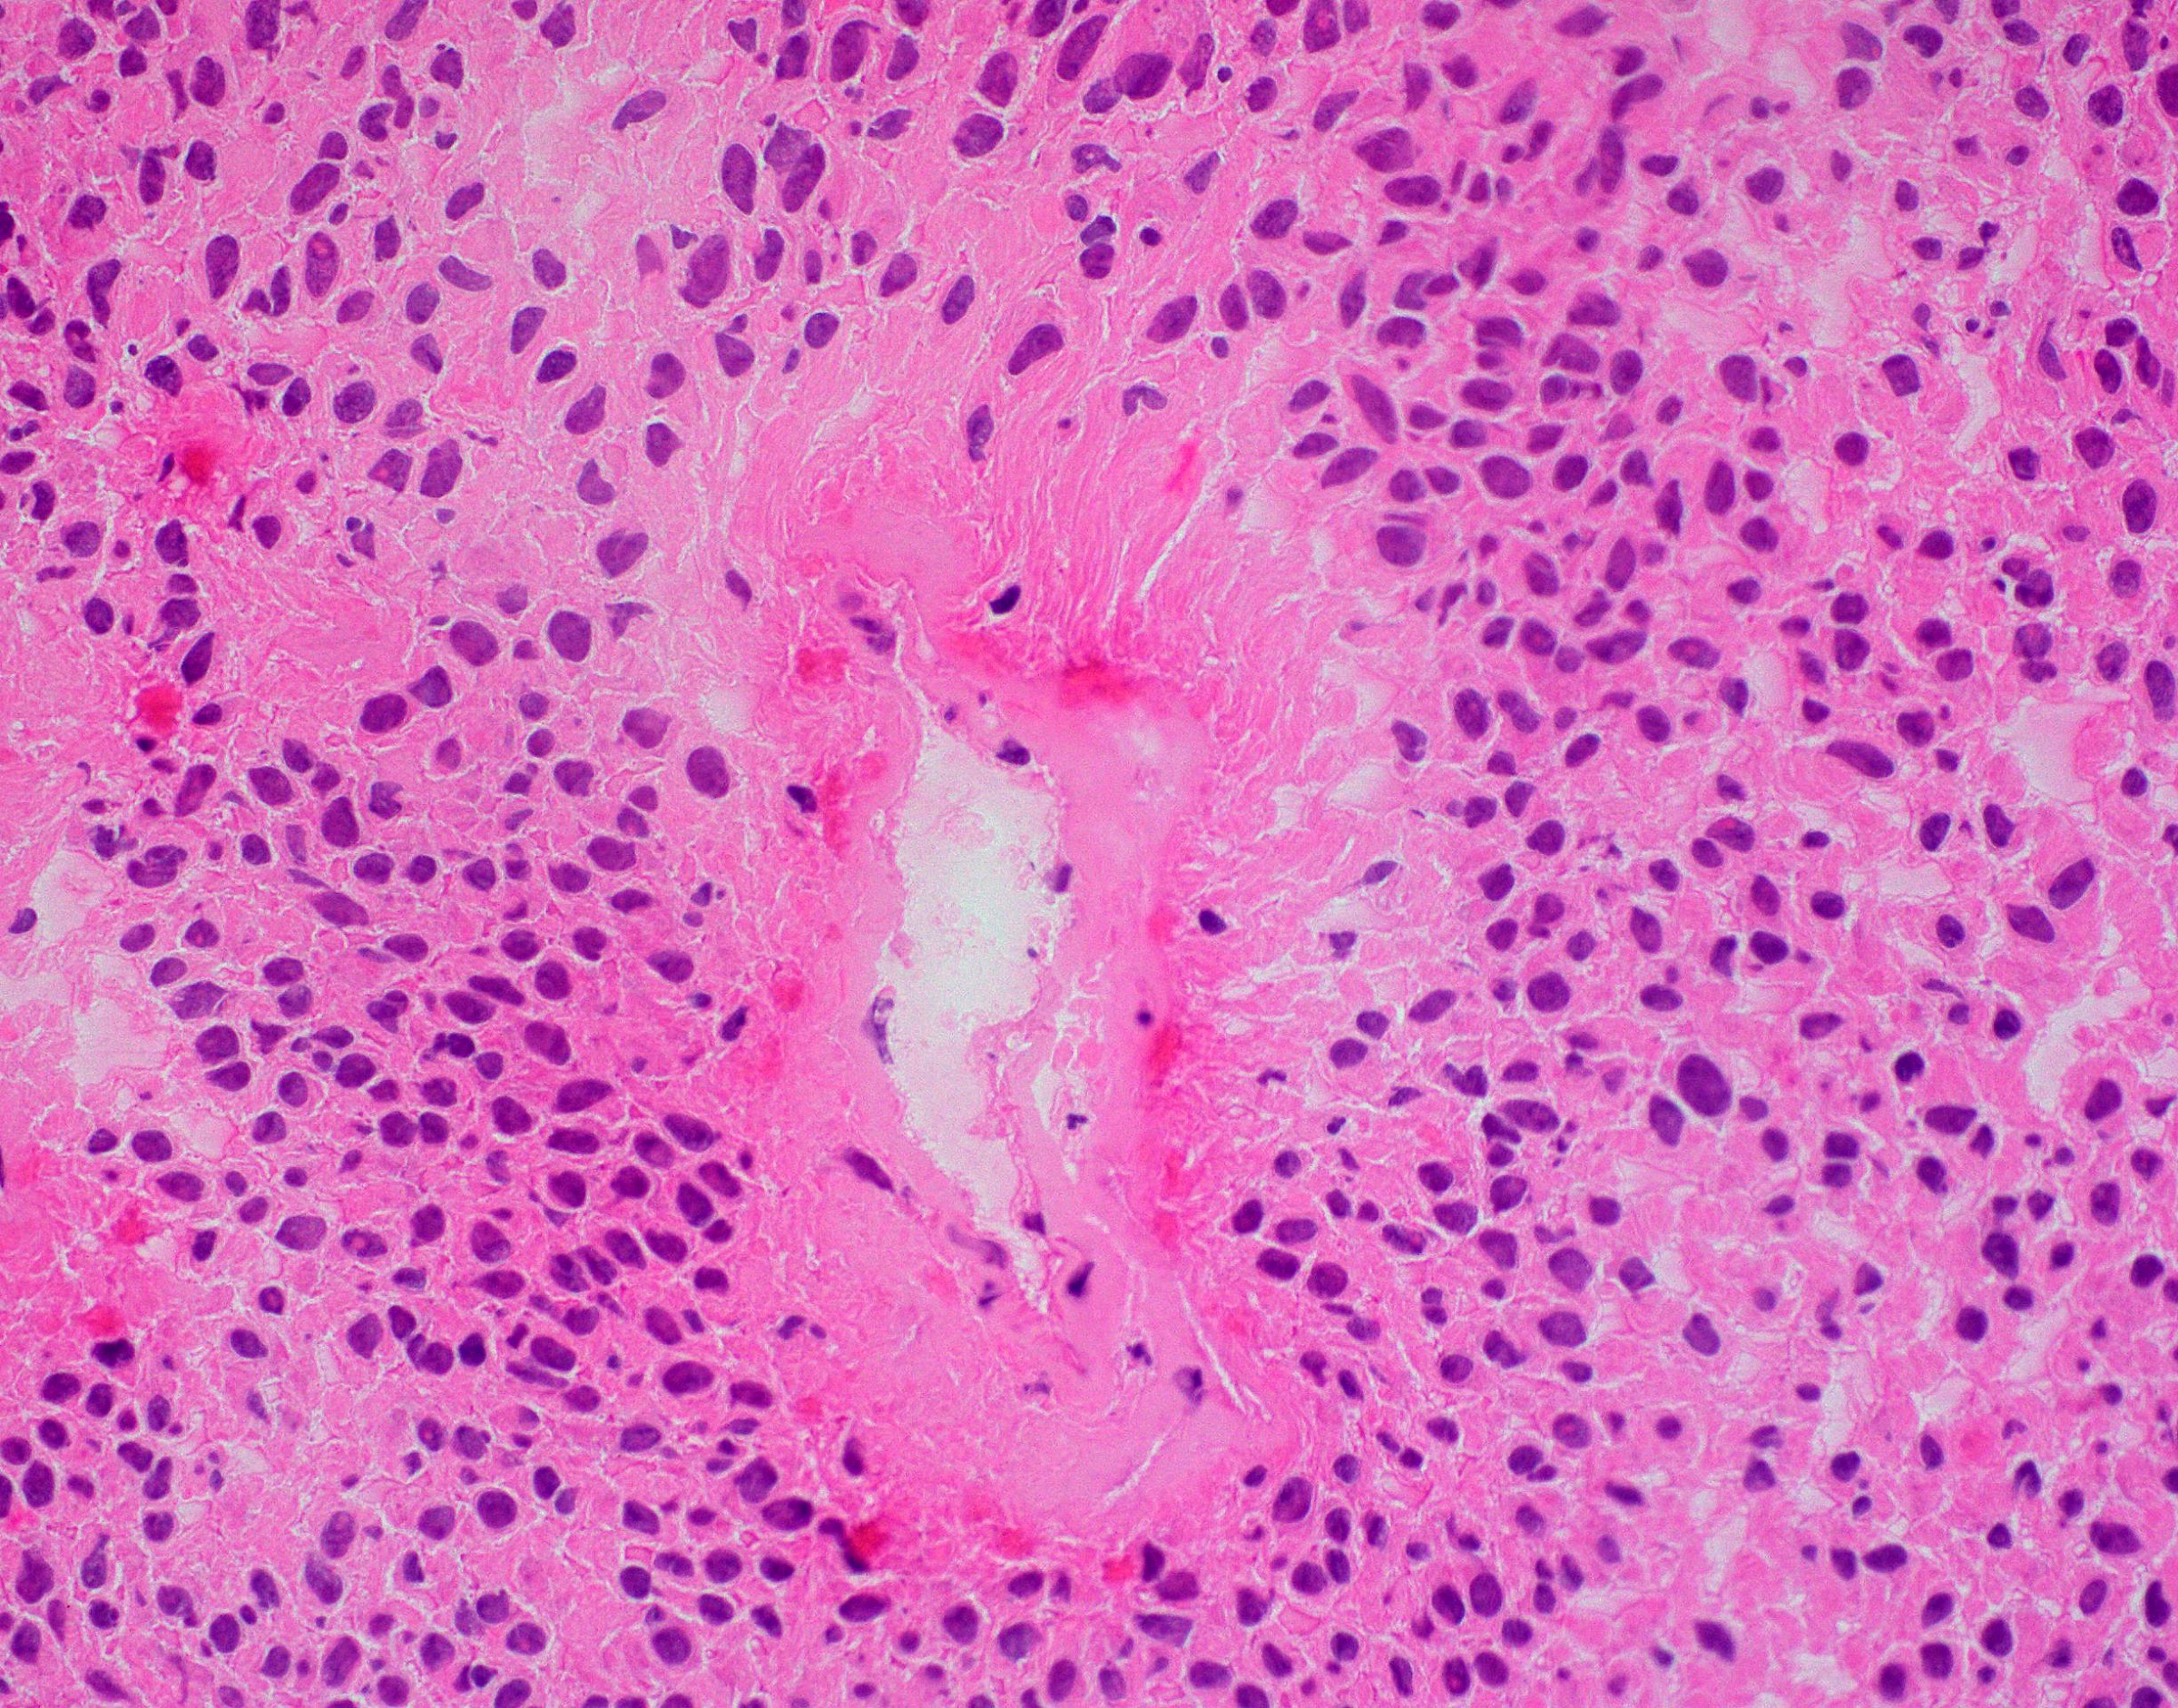

Microscopic (histologic) description

- Perivascular pseudorosettes, true ependymal rosettes, lumina and fibrillar areas

- May see gemistocyte-like cells and hypercellular nodules, particularly in posterior fossa tumors

- Can have nonpalisading necrosis, areas of cystic or myxoid degeneration, calcifications, degenerative atypia, neuronal differentiation and rarely metaplastic elements

Microscopic (histologic) images